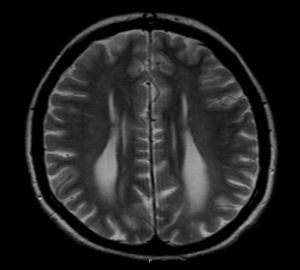

A 39 year-old female with Turner Syndrome completely asymptomatic in the previous years, presented to our department with recent onset of dizziness and fatigue.